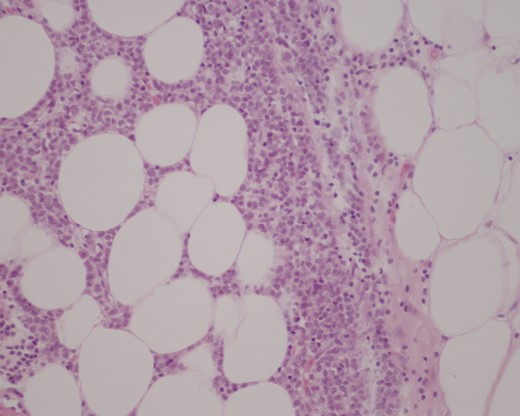

Histopathological examination of the resected specimens showed a 3-cm intraluminal gallstone within the proximal ileum, with focal metastatic carcinoma consistent with breast primary present in the adjacent mesenteric adipose tissue (Fig. 3), while the more distal, strictured ileal segment revealed mucosal and transmural involvement by metastatic breast carcinoma (Fig. 4). The tumour cells were strongly positive for cytokeratin, oestrogen receptor and focal progesterone receptor (<5%), consistent with metastatic breast carcinoma. They also displayed a mixed ductal and lobular differentiation pattern.

Haematoxylin and eosin (H&E) stain of proximal ileum showing focal metastatic breast carcinoma in mesenteric tissue (medium power field).